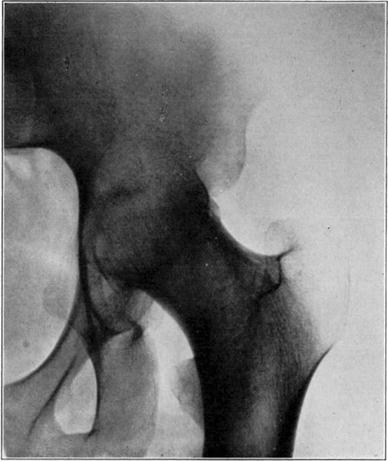

Necrosis of the proximal fragment in complete intracapsular fracture of the neck of the femur occurs in a not inconsiderable percentage of the cases. Santos [7] has recently completed a detailed study which has thrown light on many aspects of the condition. A summary of his report follows: Necrosis may occur in fractures at any age, and although relatively more frequent in older persons, it is often absent in them. This may sometimes be because of blood reaching it by way of vessels in the untorn periosteum. The vessels of the ligamentum teres may supply adequate blood to keep the head alive even in the aged.

Death of the proximal fragment predisposes to non-union, but union occurs in a considerable percentage of the cases with a dead head in which there is impaction of fragments or in which there is efficient reduction and fixation of fragments, the best results apparently being obtained from the closed abduction method of Whitman. At the end of the period of immobilization the distal living fragment usually shows roentgen-ray signs of reduced density due to atrophy of disuse, but the necrotic head which cannot atrophy casts practically as even and heavy a shadow as at the time of fracture. This usually makes it possible to diagnose necrosis roentgenologically at this stage.

If bony union occurs the head is gradually invaded by the ingrowth of tissue from the distal fragment and sometimes from the hypertrophied round ligament. The necrotic marrow is replaced by vascular connective tissue and eventually by bone marrow, but the necrotic bone is much more slowly absorbed and replaced by a variable amount of irregularly arranged living bone. The necrotic cartilage is slowly absorbed and replaced by fibrous tissue, fibro-cartilage, and to some extent eventually by new hyaline cartilage. If too much weight is borne on the head before it has been transformed into new bone, its weight-bearing portion may collapse with a resultant deformity and a poor functional result, but this may be averted by prolonged avoidance of weight-bearing. The functional stimulation which comes from motion of the limb without weight-bearing is sufficient to hasten transformation of the head.

Necrotic femoral head casting heavier shadow than surrounding atrophied living bone.

Roentgenogram of slice of excised head in Fig. 7, showing old necrotic bony trabeculae still undisturbed.